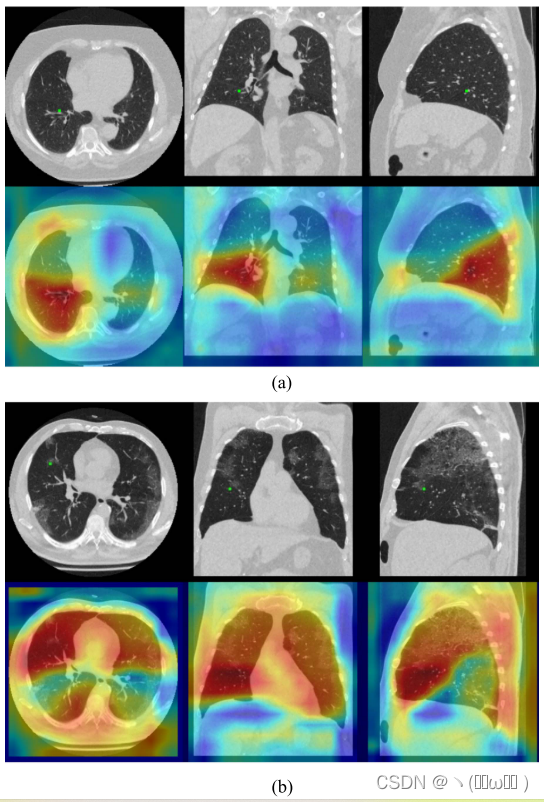

为了研究特征之间的结构化关系,我们在给定特征图x和几何特征 μ 的情况下,可视化了位置i处特征的自我注意权重。我们对新型冠状病毒肺炎测试装置的两次ct扫描进行了第一阶段RU-Net的正向传递。注意权重是来自等式2的与f(xi,x j ) τ(μ i,μ j) 相对应的自注意矩阵中的第i行向量。图4 (a) 显示了位置i的特征 (绿点) 主要取决于健康肺存在时肺叶内的信息。我们还可以清楚地看到注意力权重跟随肺叶边界。图4 (b) 显示了多个毛玻璃病变的病例,其中代表右中叶附近区域的特征与在整个肺中呈现其他区域的特征之间的相互作用。有趣的是,我们注意到,通过在非局部模块中引入几何术语,注意力权重也对应于肺边界框。

图4:来自提议的非局部模块的Self-Attention权重(第2行),用于使用原始输入扫描(第1行)中的绿点显示其位置的特征。 我们为此图使用彩色地图喷射 [39]。 显示了来自 COVID-19 测试集的两次扫描。 (a) 主要展示了清晰肺叶内的特征依赖性。 (b) 表示当目标叶受到疾病影响时需要长期依赖。